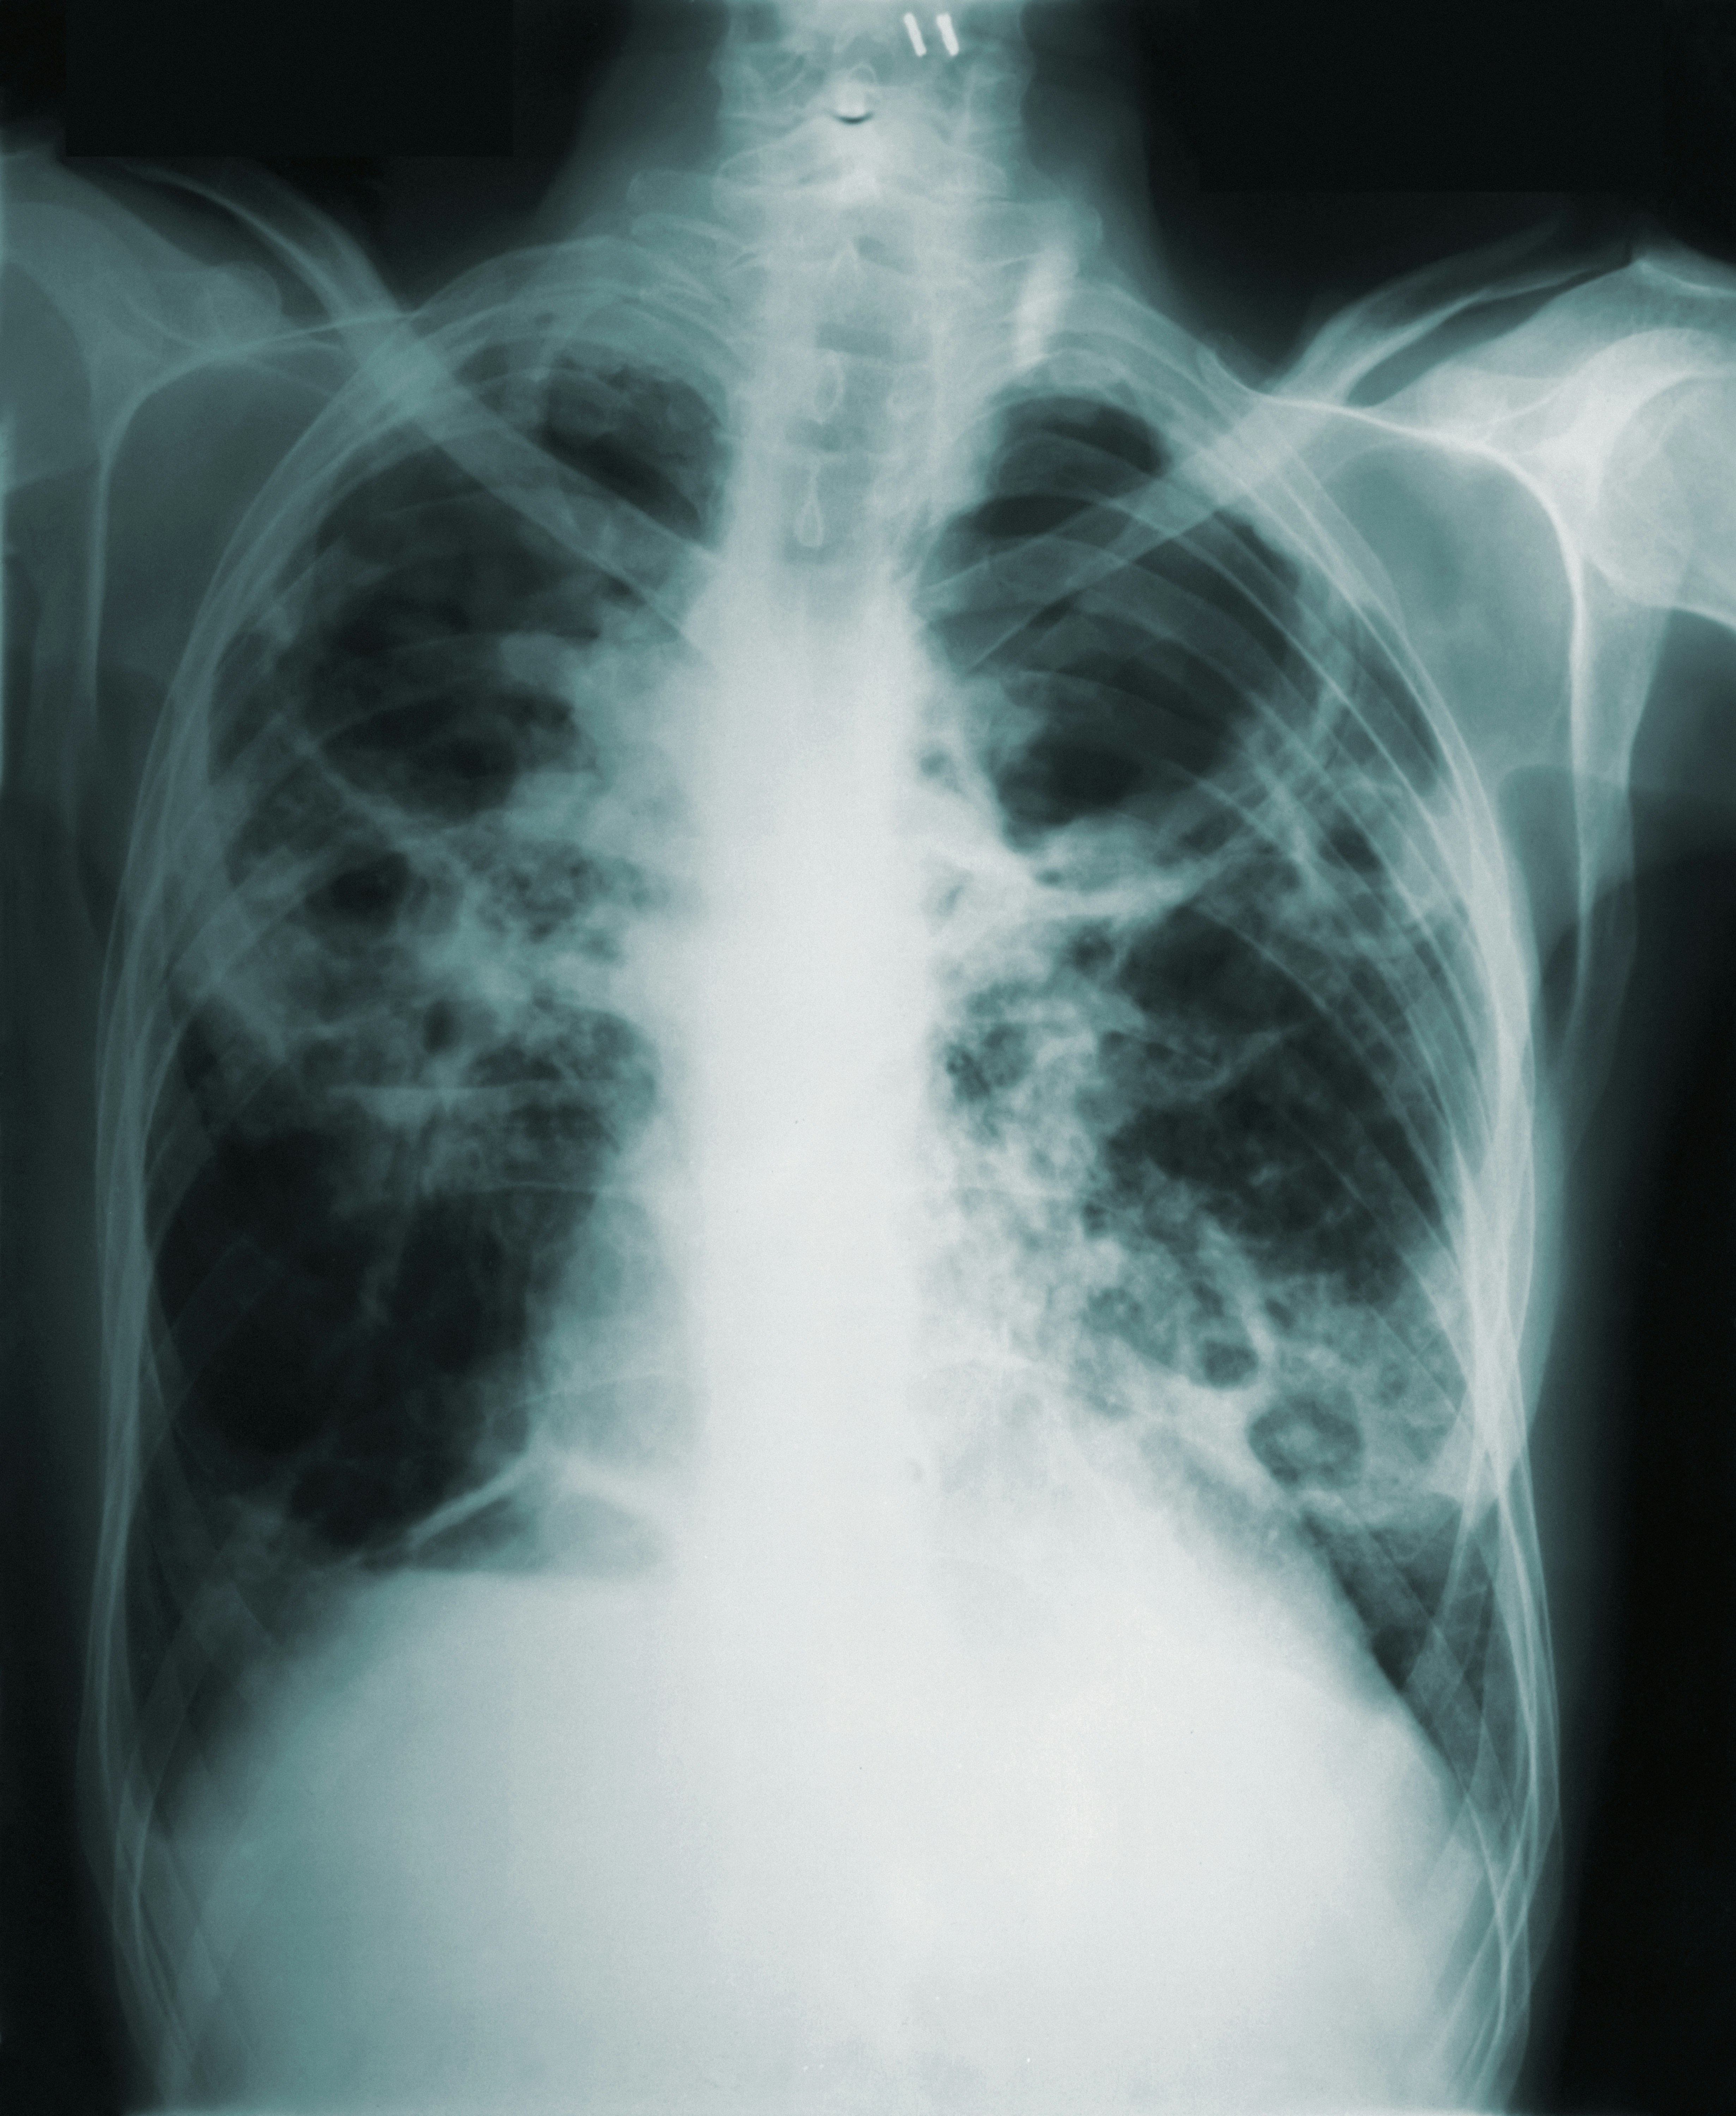

India accounts for one in four cases of tuberculosis (TB) globally, according to a new report by the World Health Organization (WHO).

Apart from contributing the highest number of cases, India also has the highest number of multi-drug-resistant TB (MDR-TB) cases worldwide.